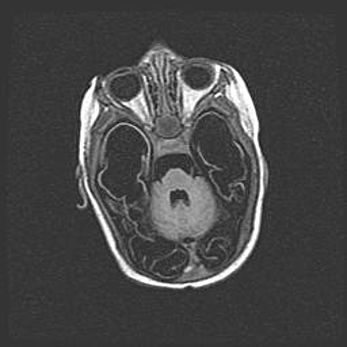

Аномалия Денди-Уокера. Признаки гипоплазии мозолистого тела.

Возраст: 5 месяцев 3 дня

Вес: 5550 г

Пол: мужской

Окружность головы: 39 см

Срок гестации: 40 недель

Аномалия Денди-Уокера – это порок развития головного мозга, для которого характерна триада симптомов: гипотрофия или аплазия червя мозжечка и/или полушарий мозжечка, расширение четвёртого желудочка с формированием ликворной кисты задней черепной ямки, гипертензионная гидроцефалия различной степени.

Гипоплазия мозолистого тела относится к дефектам внутриутробного этапа развития мозговой ткани, возникающим в процессе закладки структур головного мозга, что происходит на начальных этапах развития эмбриона.